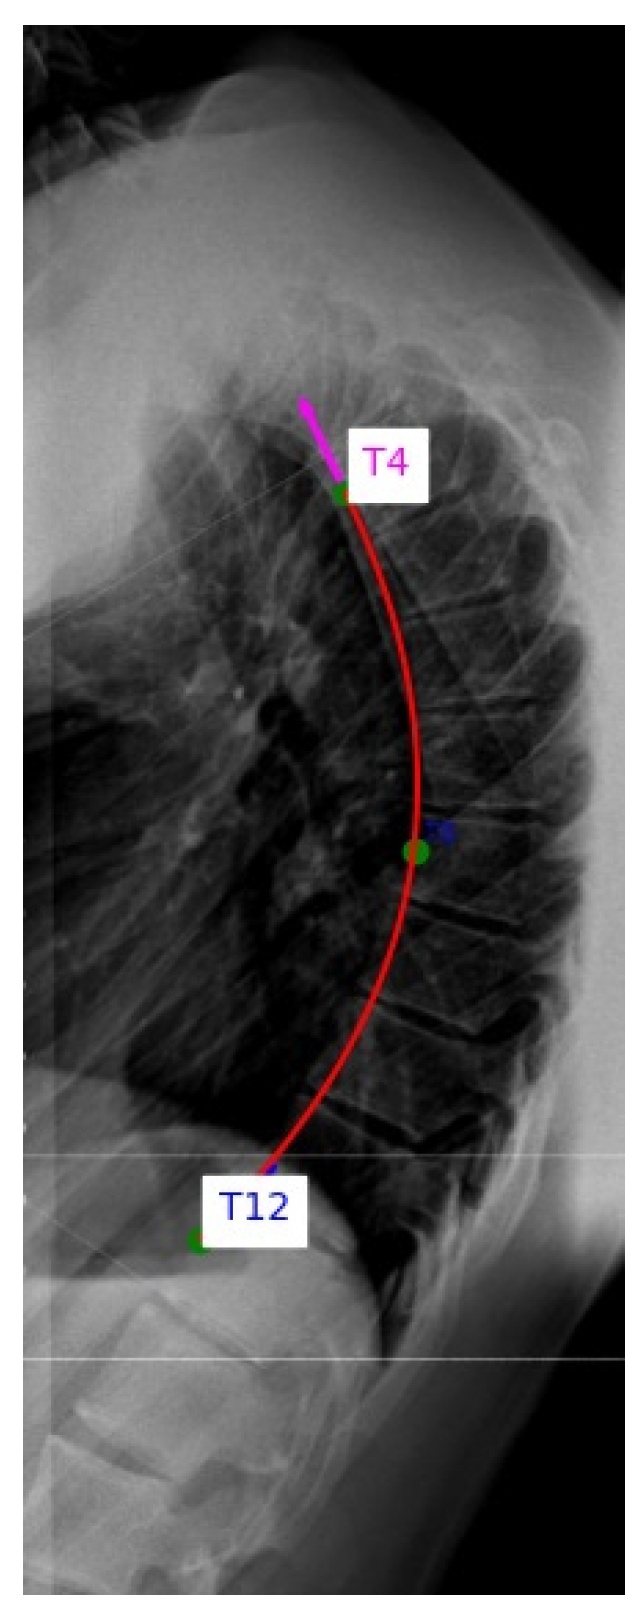

Annotations, angle calculations and data management were performed using a custom Python 3.13.6 program developed for this study. This program enabled interactive landmark selection, automatic spline and circle fitting, angle computation and systematic recording of all results for downstream analysis (Figure 1).

Figure 1. Custom Python tool for thoracic spine curvature analysis. The rater manually selects anterior wall midpoints of the triplet on lateral X-rays. The tool enables interactive landmark selection, automated spline and circle fitting and kyphotic angle calculation.